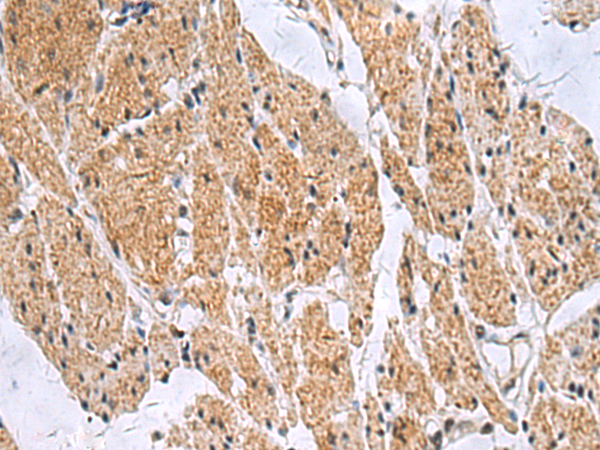

IHC (Immunohistochemistry)

(Immunohistochemistry of paraffin-embedded Human esophagus cancer tissue using SLC4A3 Polyclonal Antibody at dilution of 1:35(×200))